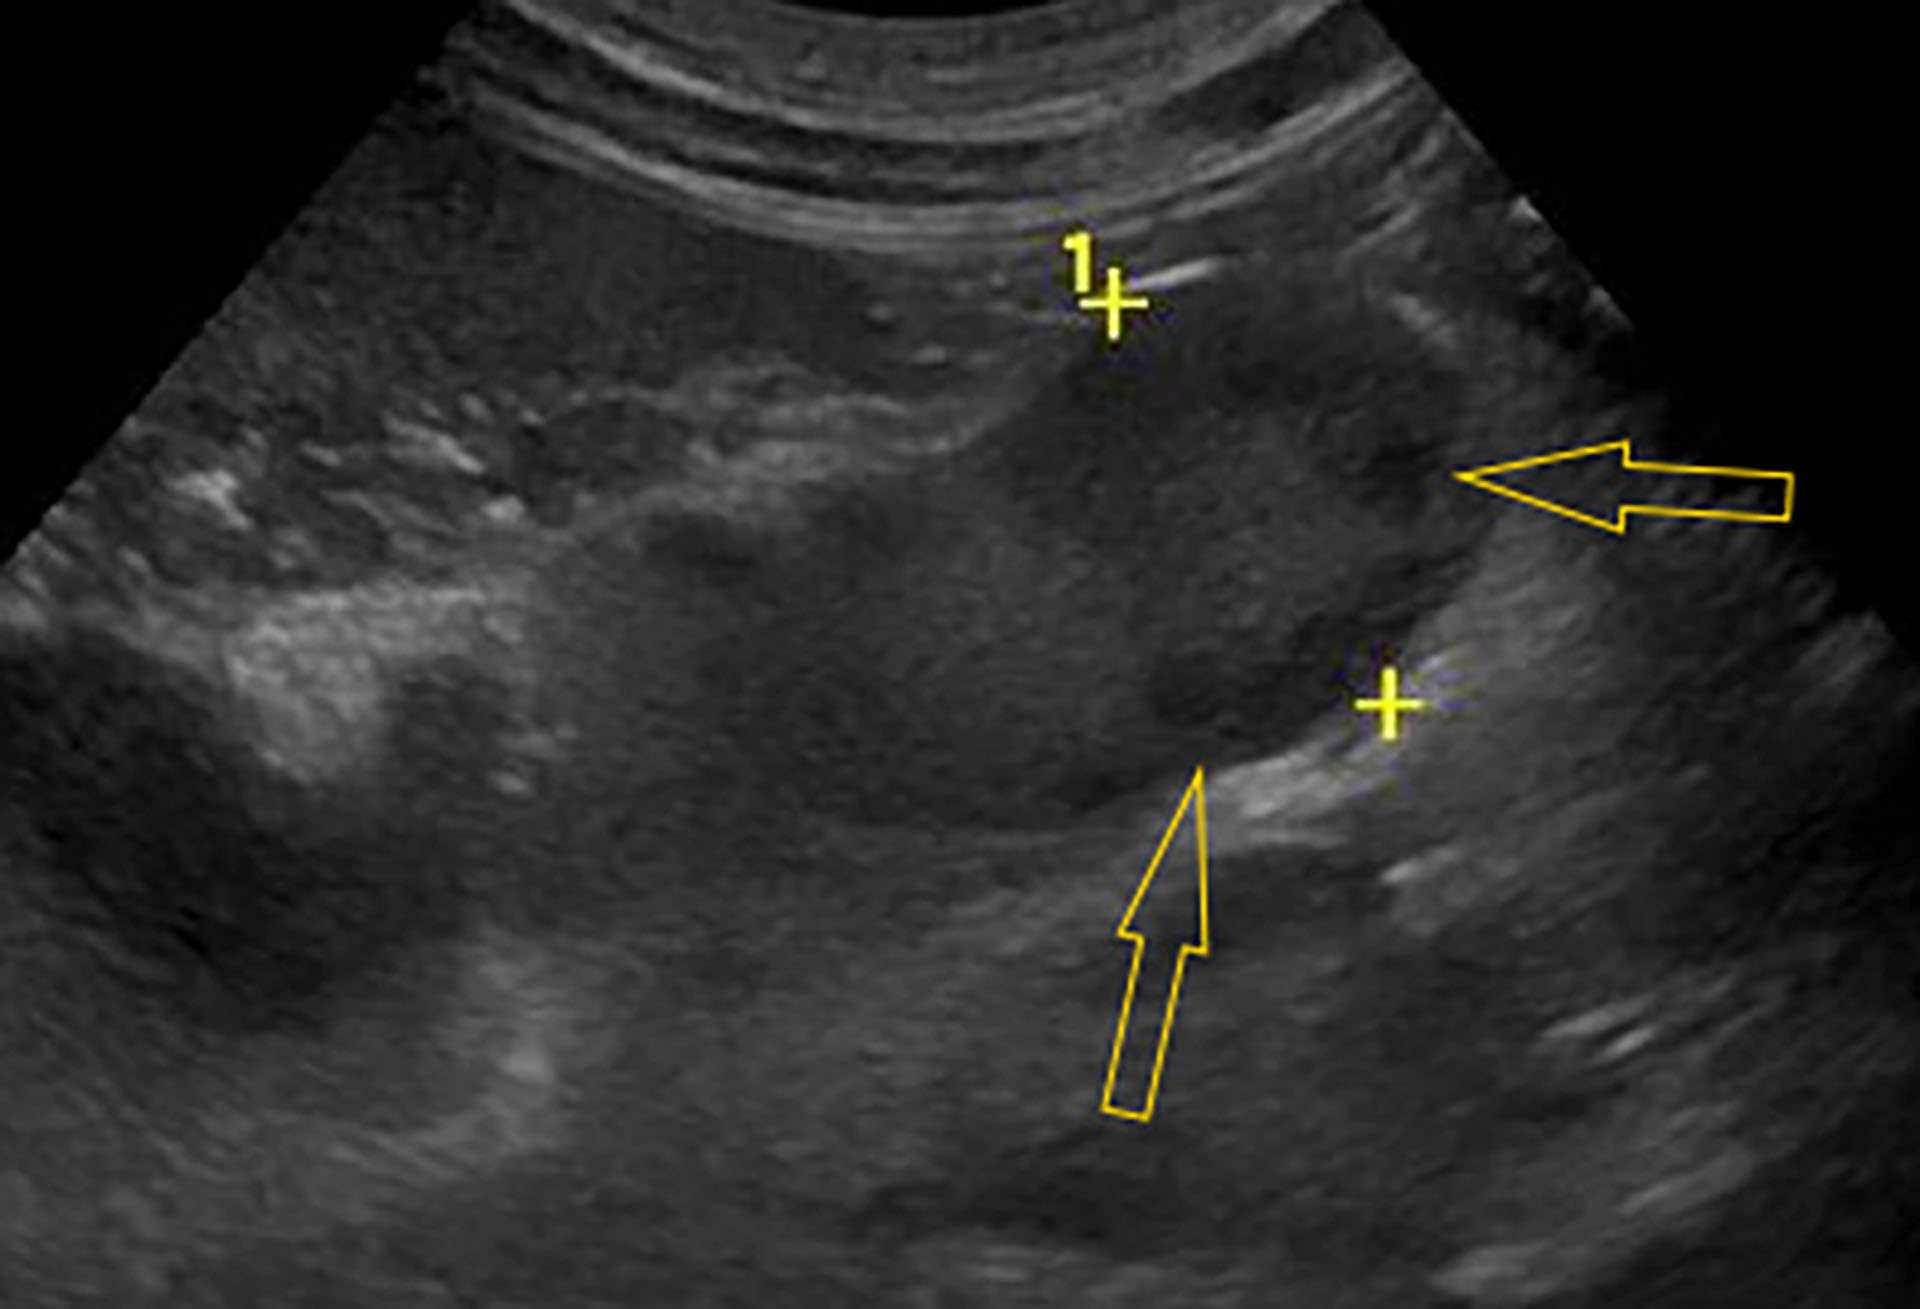

Figur 1. Ultralyd av en forstørret og hypoekkogen mesenteriell lymfeknute med bredde 14,4 mm (gule kryss) og parenkymale anekkogene foci (gule piler).

Foto: Maria Hære

Det ble funnet forstørrede mesenterielle lymfeknuter som viste seg å være strukturen som kunne kjennes ved bukpalpasjon. De mesenterielle lymfeknutene (Figur 1) målte opp mot 14,4 mm i bredden (Ref .< 8 mm), var heterogene med hypo- til anekkogene foci i parenkymet, og med hyperekkogent omkringliggende krøs forenlig med fokal reaksjon. Ileum hadde fortykket tarmvegg, målt til 5,7 mm (Ref. 2-4 mm). Milten ble vurdert som forstørret og med et noe grovt parenkym. Resterende tarm og bukorganer ble vurdert som normale.